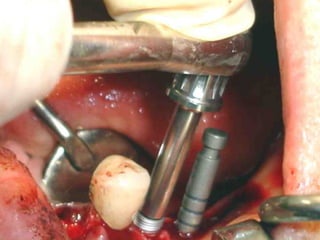

Implantes Bicon

Implantes Bicon, con menor longitud y mayor area de contacto

Implantes Bicon, conmenor longitud y mayor area de contacto